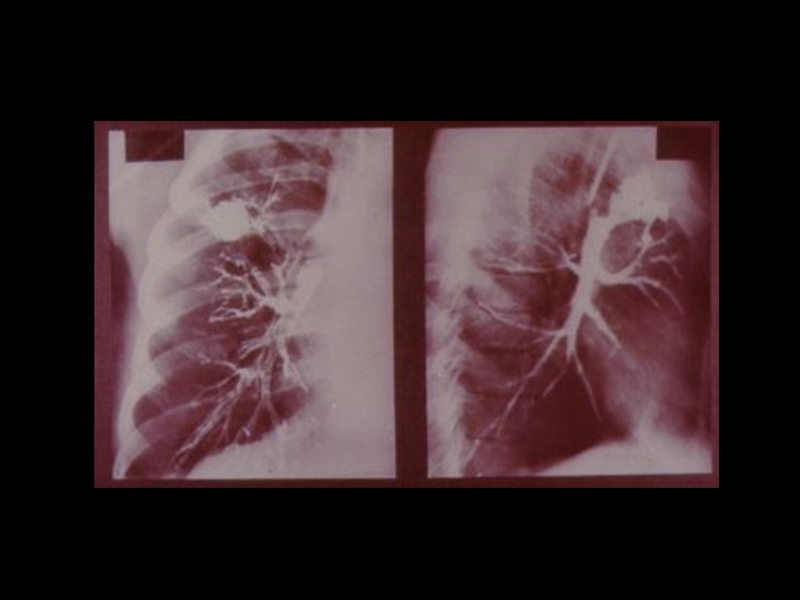

Слайд 18Методы традиционной рентгенодиагностики:

1. Общие методы

(рентгеноскопия, рентгенография)

2. Частные

методы

(флюорография, томография,

электрорентгенография, маммография и

другие)

3. Специальные методы

(урография, бронхография, ангиография,

лимфография, пневмоартрография и другие)

Методы традиционной рентгенодиагностики:1. Общие методы   (рентгеноскопия, рентгенография)2. Частные методы   (флюорография, томография,